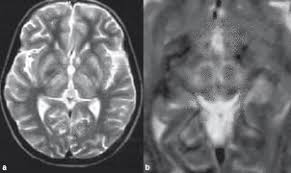

6 8 Neurologic WD is one of the main forms of the disease. In Wilson disease WD T2T2weighted T2w MRI frequently shows hypointensity in the basal ganglia that is suggestive of paramagnetic deposits. It is currently unknown whether this hypointensity is related to copper or iron deposition.

Wilsons disease is an inherited disorder in which defective biliary excretion of copper leads to its accumulation particularly in the liver and brain. The patients were scanned using spin-echo SE sequences. Wilsons disease WD is due to excessive copper accumulation in the liver and brain 1.

The neurologist was looking for typical symptoms. Wilson disease also known as hepatolenticular degeneration is a multisystem disease due to abnormal accumulation of copper. It is characterized by early onset liver cirrhosis with CNS findings most frequently affecting the basal ganglia and midbrain.

1 In addition a second miniature panda face can be seen in the high signal abnormality in the pons figure C. To describe the spectrum of brain abnormalities in Wilson disease hepatolenticular degeneration as depicted at magnetic resonance MR imaging and computed tomography CT and to relate these findings to neurologic and hepatologic abnormalities.